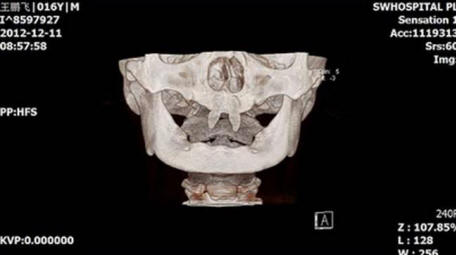

Il ragazzo cinese crebbe due denti anteriori molto affilati, dentro facendolo sembrare un vampiro. Nel dicembre 2012 la madre di nome Wang Hui portò suo figlio Wang Penfei nel locale ospedale per esame. Chongqing Municipal Boy After la nascita sta crescendo molto male e nella sua bocca sono comparsi due acuti zanna.

Wang Hui ha cercato di scoprire il motivo dell’apparizione del figlio di questi formazioni anormali e visitato innumerevoli medici, ma non ha portato molto successo. Medici di Southwestern Hospital dice che suo figlio può essere fatto chirurgia solo quando diventa adulto.

foto da fonti aperte

Il costo di questa operazione può variare da 70.000 a 80.000 RMB, sono circa $ 15.000. Secondo Wang Hui, suo figlio sta diventando sempre più ritirato, e spesso combatte con i compagni di classe, che bisbigliano di lui o lo guardano con aria interrogativa.